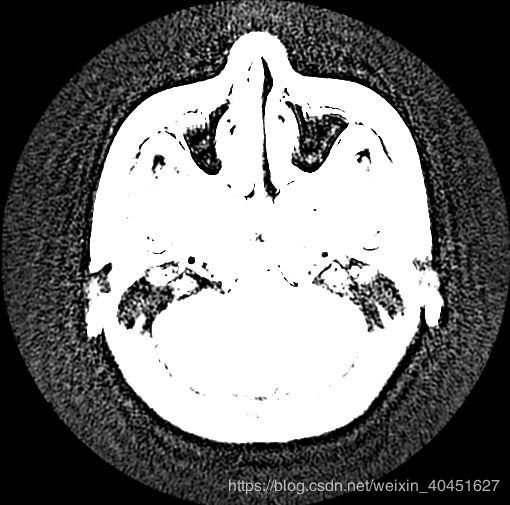

借助Image模块

data_img.show()

一条指令即可,但是效果很差,如图所示:

综合来看,两种方法都不是很好.